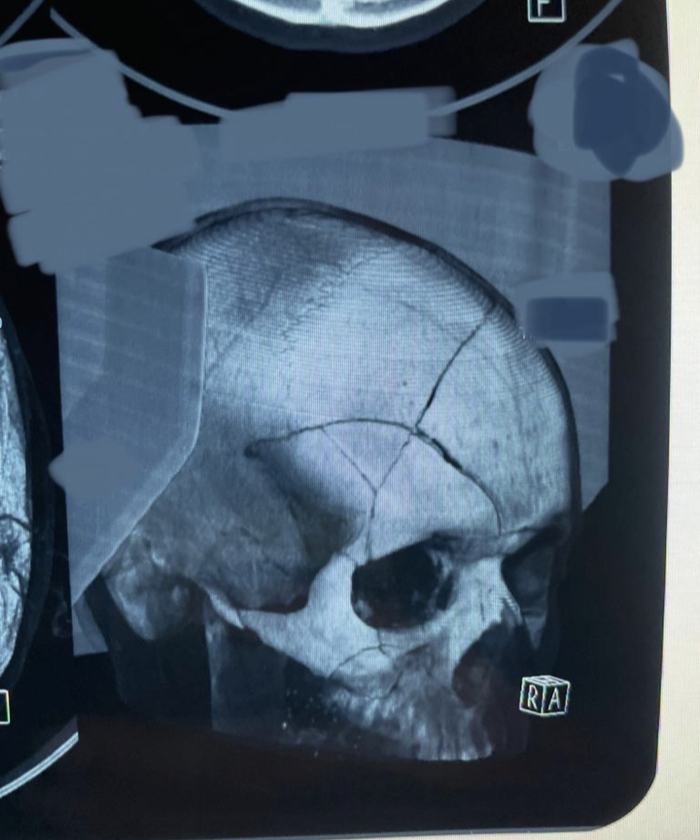

В рф сделал нормальное КТ

Понятно стало почему он постоянно обезбол просил)